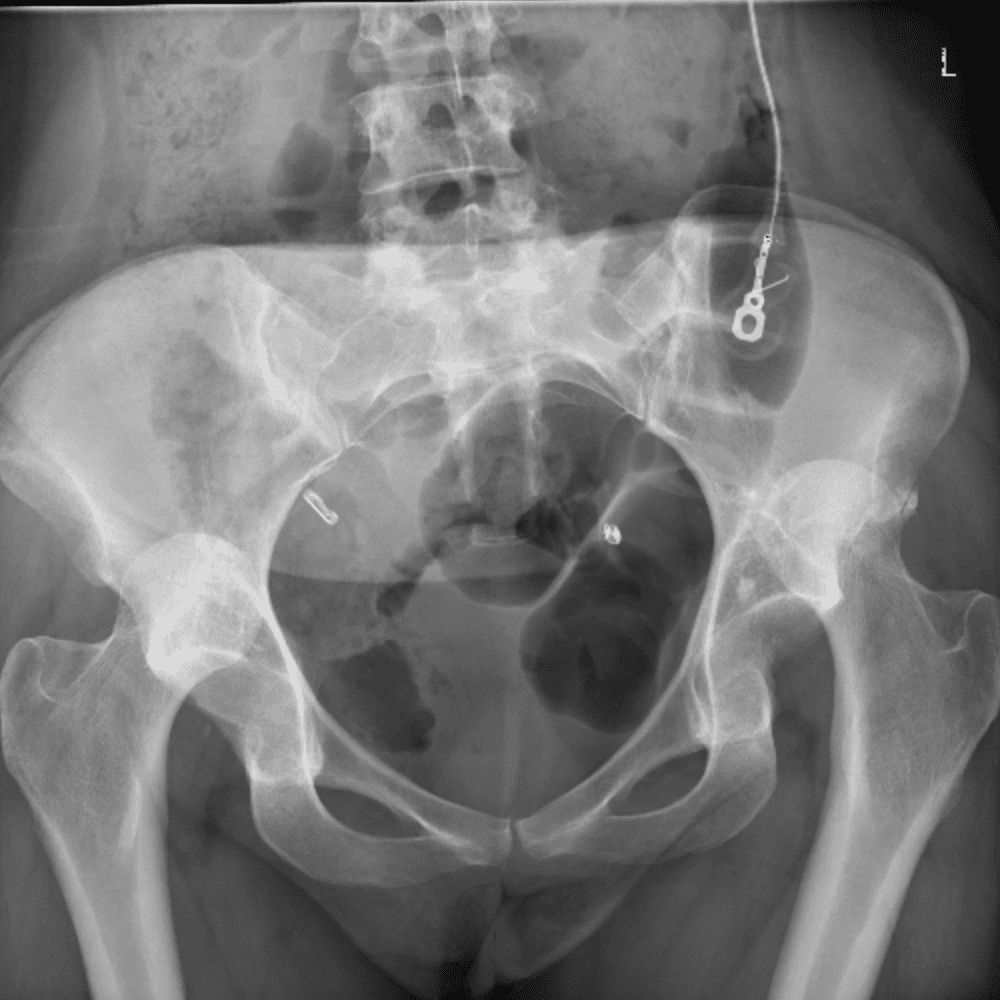

通过包含微妙或困难的病例和一些正常病例来模拟值班。